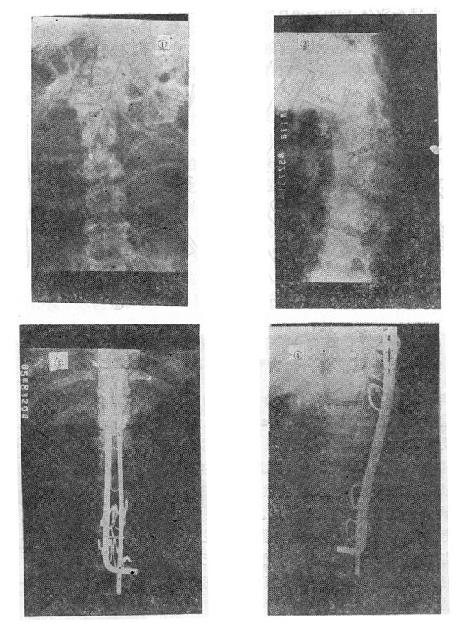

(三)爆裂型骨折的治疗 如不合并严重的神经系统症状,损伤又在两周以内者,可以用双Harrington法,撑开矫正,或用Dick手术;可以获得满意的结果(图73-13)。复位后需融合相邻两个椎间隙,因为CT常显示在爆裂型骨折中,相邻的上、下两个椎间盘均有损伤,如不融合,日后取棍后会出现腰痛。使用本法时,如前纵韧带完整,则很容易恢复椎体前方的高度。但爆裂型骨折存在下述三种情况时,需行前路减压术:①合并神经系统症状较重者;②就诊较晚,已两周以上者(常常10天以上就复位比较困难);③脊柱CT扫描显示已有较大的骨折片突出椎管内,使髓腔管变窄超过30%以上者,预示后纵韧带已有明显损伤,使用后路手术方法已无法使骨折片复位。Kostuik复习了日本和多伦多治疗脊柱骨折的结果后证实,前路减压术能使膀胱、肛门及肢体功能得到更好的恢复。

爆裂型骨折的治疗

图73-13 爆裂型骨折的治疗 ①术前,骨折脱位;②术后,侧位;③术后,正位

(五)切片状骨折的治疗 因为这种骨折伴有整个韧带的完全撕裂,且常合并截瘫,用Harrington撑开棍治疗后方间隙反而会明显增宽。应选用强度较好的Luque或Dick装置为好,不仅能获得满意的复位(图73-16①~③),而且固定牢固,术后即可随意翻动病人,术后1-2即可让病人起床坐轮椅活动,有利于截瘫病人的康复与护理。

切片骨折的治疗

图73-16 切片骨折的治疗